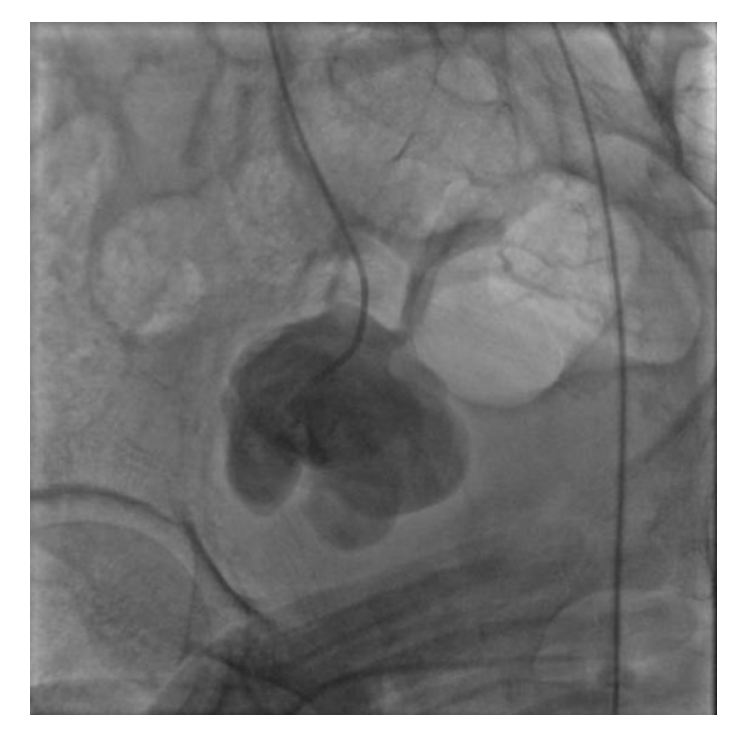

The first patient was a 44-year-old male without medical history, who developed an acute pain the day following an intramuscular injection in the right gluteal muscles, with paraesthesia and paresis of the right inferior limb. Three months later the patient presented in the emergency department due to worsening pain. Computed tomography scan (CT scan) identified a pseudoaneurysm in the right gluteal region arising from a branch of the right internal iliac artery which was most likely the inferior gluteal artery (IGA) (Figure 1). We performed a cross-over catheterisation and angiography of the right internal iliac artery which showed a contrast leakage of the IGA (Figure 2). We performed an embolization of the pseudoaneurysmal sac using 15x20 cm and 20x30 cm coils and embolization of the origin of the IGA using 12x30 cm and 10x20 cm coils (Figure 3). A CT scan was done 48 hours after and showed a profound hematoma of the right gluteal region without signs of contrast media extravasation. The day after, the patient benefited from drainage of the hematoma through a right retroperitoneal anterior incision (Figure 4). Transfusion of 2 units of blood was necessary after surgery. He had an uneventful recovery.